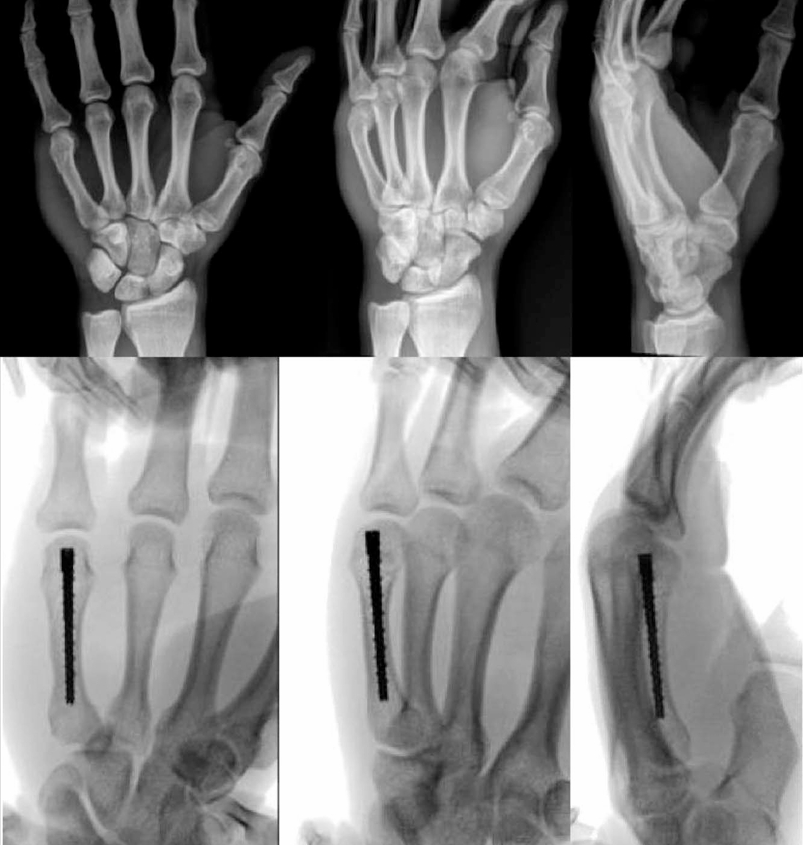

5. Intramedullary Screw Fixation for Metacarpal Neck Fractures

Intramedullary Screw Fixation.png

6. Intramedullary Screw Fixation for Multiple Spiral Metacarpal Shaft Fractures